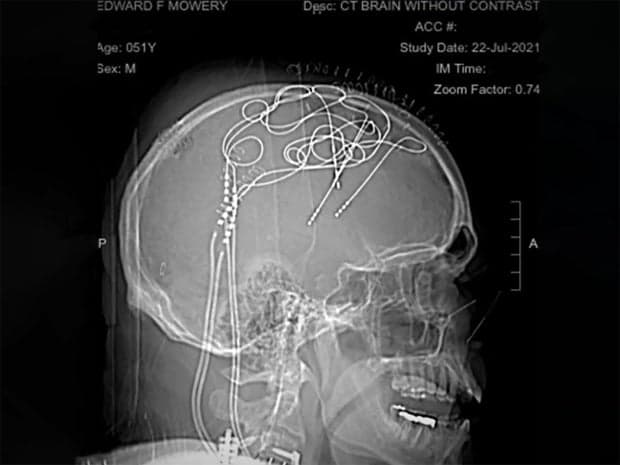

Ed Mowery đã tự nguyện tham gia một nghiên cứu về kích thích não sâu và cơn đau, trải qua ba ca phẫu não. "Tôi có những nút gân lộ ra ngoài đầu," Mowery nói. "Và tôi có 144 dây dẫn tới hai máy tính. Tôi còn đội một chiếc khăn quấn đầu và tóc tôi cũng nhiều hơn nhiều!"

Các nhà nghiên cứu đã cấy ghép điện cực vào não Ed Mowery, giúp xác định các vùng não và tín hiệu thần kinh liên quan đến cơn đau của anh. UCSF

Gupta cho biết, "Sau vài tuần, họ đã có thể liên kết giữa cơn đau của Ed và những thay đổi trong não. Và họ phát hiện với Ed không chỉ có thể dự đoán khi cơn đau sắp xảy ra, mà còn có thể định lượng mức độ đau dự kiến, đồng thời có thể ngăn chặn cơn đau bằng cách kích thích một chút. Ngay cả trước khi cơn đau nhận thức được, bộ kích thích đã hoạt động và bắt đầu can thiệp vào chu trình đau."

Gupta dự đoán câu chuyện của Mowery chỉ là khởi đầu: "Những gì các bác sĩ có thể làm, họ thực sự có thể đặt các đầu dò trên toàn bộ não và để chúng hoạt động như những thiết bị nghe tín hiệu của não Ed."

Hiện nay, một máy tính có thể nhận diện khi cơn đau của anh sắp xuất hiện – và tắt nó đi.